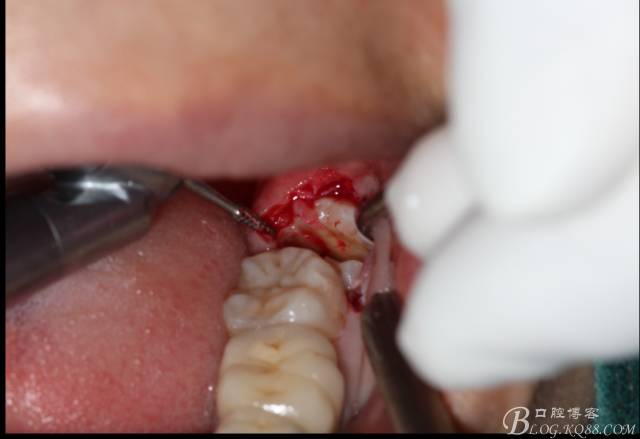

鈍性翻辨露冠

640 (10).jpg

角度鍋輪機(jī)結(jié)合冷鹽水冷卻分冠

640 (11).jpg